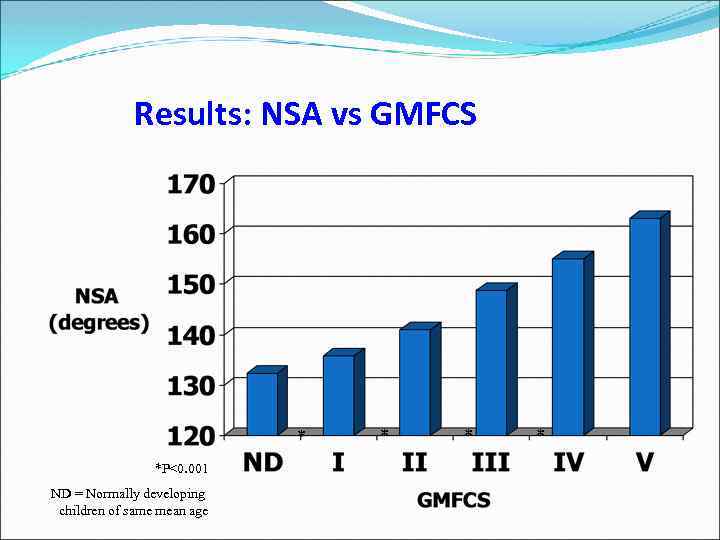

Results: NSA vs GMFCS * *P<0. 001 ND = Normally developing children of same mean age * * *